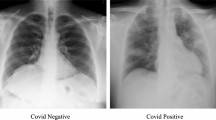

COVID-19 has become the global epidemic affecting millions of people across the world. The fact that COVID-19 spreads quickly and devastating for elderly person makes this disease lethal as we witnessed a massive mortality rate in first, second, and third wave since 2020. Early diagnosis of COVID-19 is mandatory to prevent the spread and damage control, as only few nations have been able to vaccinate more than 50% of their population. The healthcare professionals commonly use the real-time polymerase chain reaction (RT-PCR) test to identify the COVID-19. Although RT-PCR test is considered more reliable among other COVID-19 detection tests; however, sensitivity of RT-PCR lies in the range of 65%-95% and took hours to diagnose the COVID-19 disease. Therefore, there exists an urgent need to develop more rapid and reliable diagnostics methods for COVID-19. In this regard, Chest X-ray and CT scan images are also being used to determine the abnormalities in the lungs of the COVID-19 patients which are found after the initial symptoms of this disease. We exploit the benefits of convolution neural network (CNN) for reliable detection of various diseases and used it for COVID-19 detection. For this purpose, we proposed a deep learning model to automatically detect the COVID-19 disease by processing the chest X-ray images. More specifically, we presented an Inception-ResNetV2 network-based deep learning model for COVID-19 detection. Performance of our model is evaluated on the publicly available COVID-19 dataset. The accuracy of 96% indicates the effectiveness of the proposed model for COVID-19 detection.